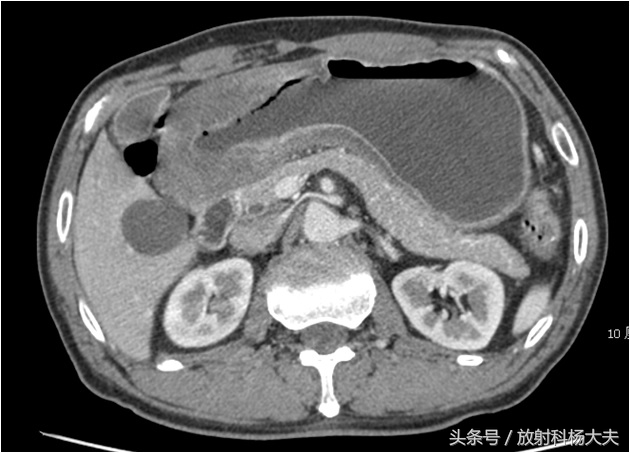

先做胃镜,在胃的角落里发现了一个肿块,取了活检,胃癌!再做CT,肝脏转移!意味着,胃癌到了晚期。

CT图:胃窦部胃壁增厚,为胃癌

肝上的低密度,为肝转移瘤